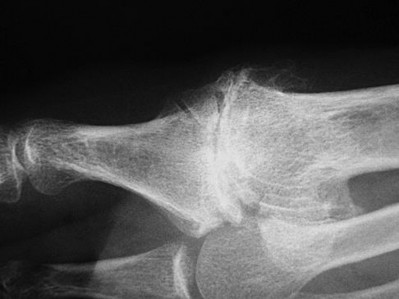

Slide 1 Slide 2 Slide 3

A 44-year-old obese man presents for treatment of acute ankle pain. He does not have a history of trauma or a systemic history of note. His opposite foot has had multiple episodes of acute pain in the past, lasting from 3 to 5 days. On examination, the

ankle is warm, swollen, and exquisitely tender to palpation and any range of motion (Slide1, Slide 2, and Slide 3). C oncerned about the source of pain, you aspirate the joint and send the sample for analysis. You expect to find: